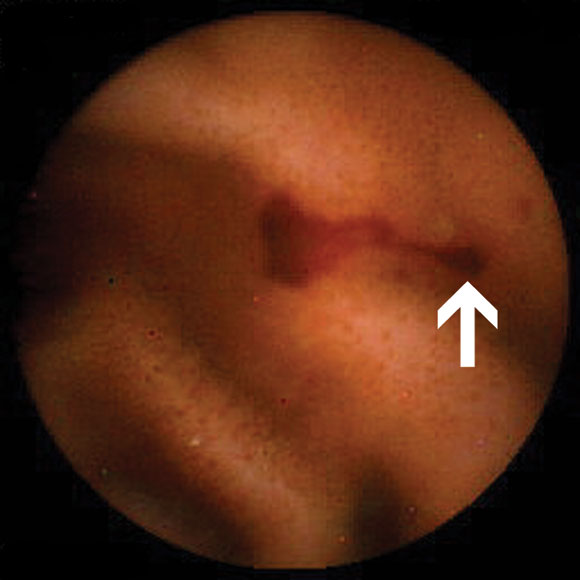

Of the nine patients referred for investigation of small-bowel Crohn's disease, none had been taking non-steroidal anti-inflammatory drugs (NSAIDs) before onset of their symptoms. Small-bowel erosions or ulcers (Box 2B) were seen in seven of these nine patients. Enteroclysis demonstrated mucosal irregularity in two of the seven patients with abnormal findings on capsule endoscopy. Management was changed in five of the nine patients. One patient was lost to follow-up. Changes in management are summarised in Box 4.

In suspected Crohn's disease of the small bowel, our results are similar to other studies. These have reported an increased yield in detecting erosions and ulcers missed by conventional investigations, including ileoscopy and small-bowel barium studies.4,13 Our findings led to a change in management in five out of seven patients followed up (Box 4). We believe that capsule endo-scopy is useful in two distinct situations. First, in investigating patients with suspected de novo small-bowel Crohn's disease based on specific criteria, including abdominal pain, fever, weight loss, anaemia, elevated erythrocyte sedimentation rate but negative results on conventional investigations.4 Second, in patients whose clinical and laboratory findings are out of keeping with the known extent and severity of disease using conventional investigations.